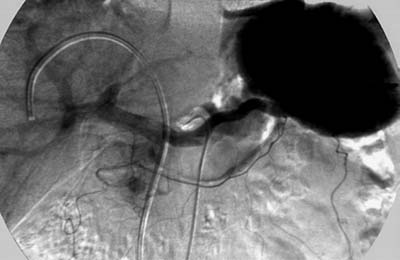

Рис. 1. Дооперационная лучевая топическая диагностика органического

гиперинсулинизма у больной М., 53 лет. Инсулинома головки поджелудочной железы.

(в) Целиакография: в венозную фазу имеется длительная задержка контрастного

вещества в образовании.